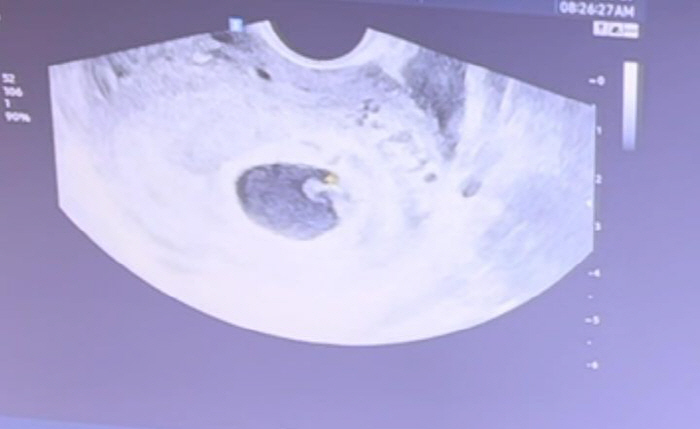

사진은 임신한 김소영 태중 아기의 초음파 사진이다.

이날 영상에서 초음파 검사를 받고 있는 김소영에게 담당 의사는 "축하드려요. 애기가 너무 잘 크고 있어요"라고 말했다.